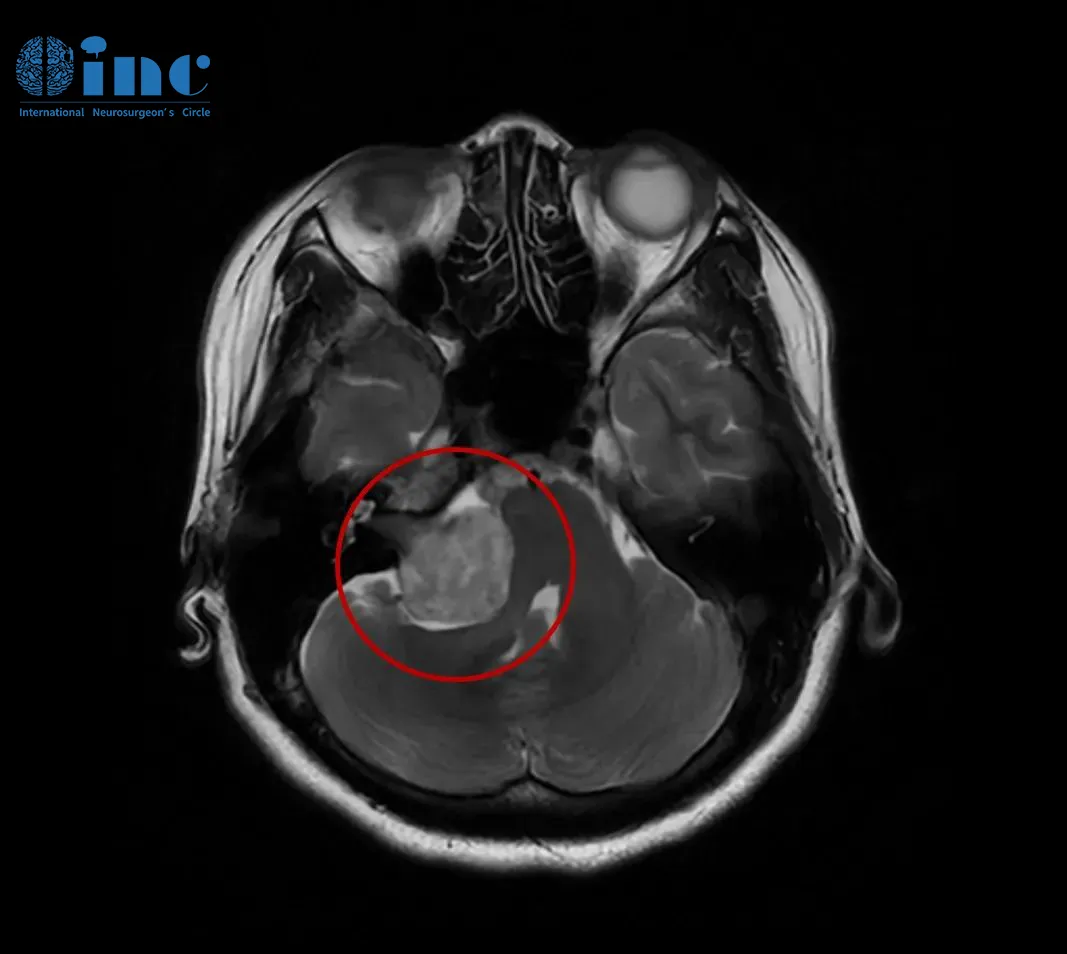

36岁的卢卡,怎么也想不到持续的耳鸣和逐渐下降的听力背后,藏着一个潜伏的肿瘤超过3cm的巨大听神经瘤。 幸运的是,卢卡最终在国际知名神经外科教授的操刀下顺利完成手术,肿瘤被完整切...